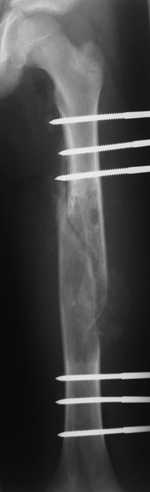

Most likely fibrous dysplasia, we had the same case but younger age patient 4 years ago treated by uniplanar ext fix followed by percut. curretage and bone marrow injection and healed well.

at this age IMN can solve the problem .

Dear colleagues, I completely agree with Dr. Freih Odeh Abu Hassan. I am not sure about ImN at this case but, in my opinion, ExFix, curretage and bone marrow injection is one of the best decision.